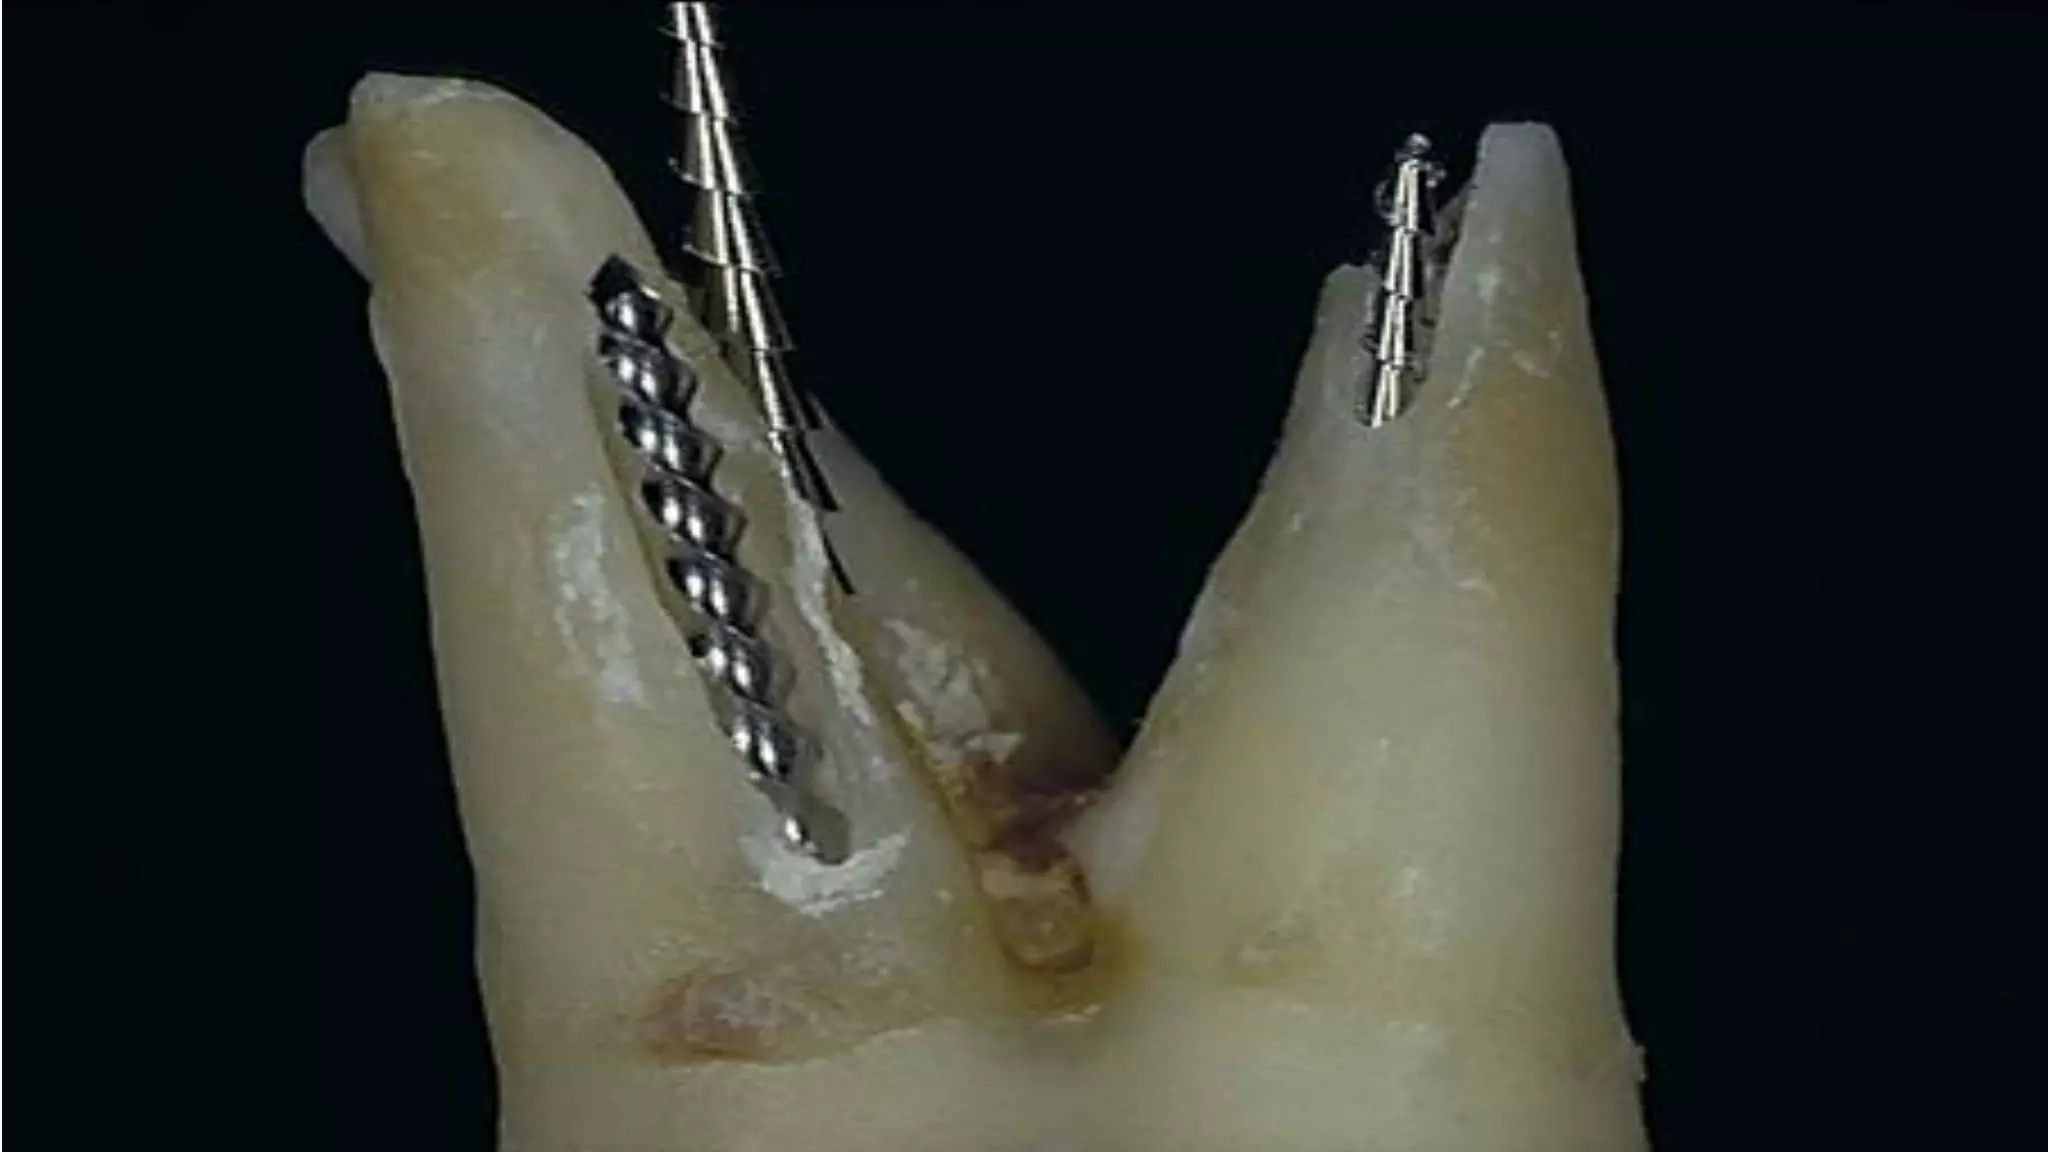

BLUNDERBUSS APEX

newly erupted tooth showing an

incompletely formed root having a

wide canal and the pulp may get

necrosed due to caries or trauma

and may require root canal

standard instrumentation and

obturation techniques are not

favorable

Open Apex

Endodontic management of the pulpless,

permanent teeth with wide open blunder buss

apex offers dentists a most difficult condition

to treat.

Problem of open apex - the open apex occurs

when trauma or caries cause pulpal exposure

prior to the completion of root development.

An open apex refer to absence of sufficient root

development to provide a conical taper to the

canal - “Blunderbuss” canal.

Since it is necessary to seal the apex to gain

endodontic success, it is physically impossible to

achieve this objective through ordinary procedure

in open apex cases. www.indiandentalacademy.com